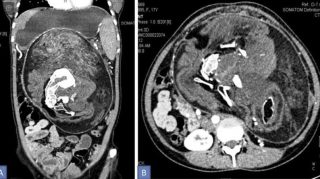

Una TAC del feto trovata nell'addome della donna Credit: Kumar, et al (BMJ Case Reports)

L’inquietante esperienza della donna è stata raccontata dai suoi medici alla BMJ Case Reports. La ragazza aveva iniziato a insospettirsi quando sul suo addome aveva visto spuntare una sorta di nodulo duro. Negli anni a venire quel nodulo era cresciuto, tanto da provocare dolore. Quando finalmente la ragazza è stata visitata, all’inizio si era pensato a un tumore. Dalla TAC sul nodulo, però, è venuto fuori che c’erano depositi di calcio che sembravano avere “la forma di vertebre, costole e ossa lunghe”.

A quel punto i medici capirono di cosa si trattava, procedendo a eliminarlo. Il feto era grande 36 x 16 x 10 centimetri, il più evoluto tra tutti i casi fino a oggi registrati. Il feto è stato subito rimosso e la 17enne si è ripresa rapidamente. Purtroppo, però, i medici non sono stati in grado di estrarre tutte le parti del feto. Alcune tracce sono rimaste all’interno della paziente. Secondo i medici esiste la remota possibilità che queste cellule crescano senza controllo, ma i continui controlli sulla ragazza eviteranno conseguenze importanti.